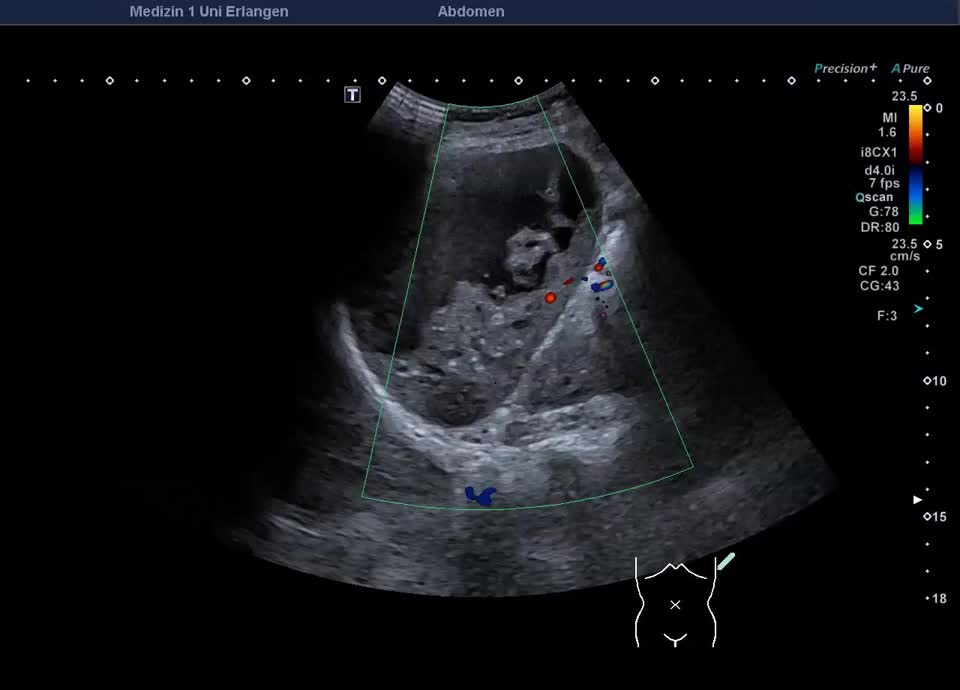

Kasuistik: 57-jährige Patientin mit einer Granulomatose mit Polyangiitis mit unklarer Leberwerterhöhung (ohne abdominelle Symptomatik). Im Ultraschall zeigt sich ein überraschender Milzbefund: Die Milz stellt sich großteils liquide dar, mit nur einem geringen Anteil soliden Gewebes, die Milzkapsel ist intakt. Die Kontrastmittelsonographie zeigt wenig erhaltenes und kontrastiertes Milzparenchym, ohne KM-Austritt in die flüssigen Anteile. Ein Trauma ist auf explizite Nachfrage nicht erinnerlich. Der Befund entspricht dem seltenen Fall einer asymptomatischen subtotalen Milznekrose, am ehesten im Rahmen einer nekrotisierenden Vaskulitis.